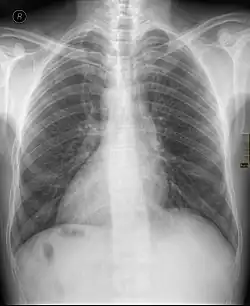

Chest X ray of a person with dextrocardia situs inversus showing the cardiac apex pointing towards right

Dextrocardia (from Latin dextro 'right hand side' and Greek kardia 'heart') is a rare congenital condition in which the apex of the heart is located on the right side of the body, rather than the more typical placement towards the left.[1] There are two main types of dextrocardia: dextrocardia of embryonic arrest (also known as isolated dextrocardia)[2] and dextrocardia situs inversus. Dextrocardia situs inversus is further divided.

Dextrocardia situs inversus refers to the heart being a mirror image situated on the right side. For all visceral organs to be mirrored, the correct term is dextrocardia situs inversus totalis.[5][6]